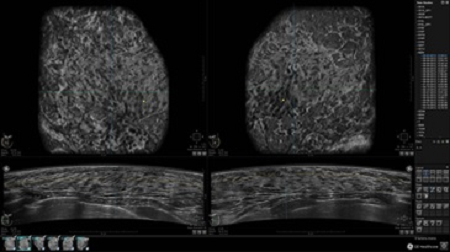

GE INVENIA ABUS – это современный УЗИ аппарат, который создан для точной и эффективной диагностики сканирования с высокой плотностью молочных желез. Выявляемость патологий раковых и предраковых стадий заболевания составляет 55%, что в конечном счете позволяет ставить врачу точные и своевременные диагнозы. Традиционные методы использования маммографии не показывают такой выявляемости, ограничиваясь лишь 3-38%.

УЗИ-аппарат GE INVENIA ABUS позволяет проводить максимально операторонезависимые процедуры, что значительно снижает риск неправильной постановки диагноза и сопутствующие издержки на обработку информации. Система готовит отчет в течение 3-х минут после сканирования, это безусловное преимущество по сравнению с обычным УЗИ сканером.

• Многооконный просмотр: 4 - 12 изображений

• Стандартизованная ориентация изображения: «толстый срез» в коронарной плоскости; поперечная; сагиттальная плоскость; радиальный и антирадиальный поворот изображения; просмотр исключительно области интереса

• Одновременный просмотр двух изображений для сопоставления в коронарной плоскости